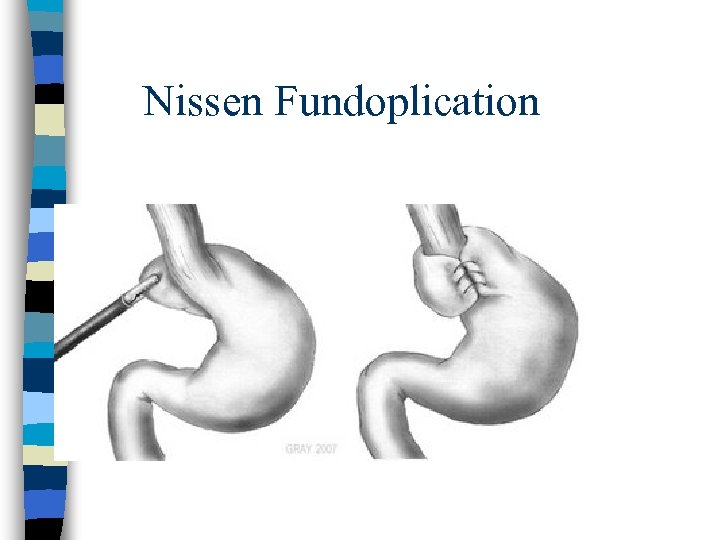

GERD Tx HOB 6 inches (not just pillows) n NO: n – – – Eating within 3 hours of bedtime, large meals Acidic foods(coffee, citrus, tomatoes, etc) Drugs (see list of contributors to sx) Smoking (hyposalivation) Foods that weaken LES (fatty foods, alcohol, chocolate, peppermint) Meds: PPI x 8 -12 weeks (better than H 2 blockers, antacids or pro-motility meds) n Weight loss n Surgical: Fundoplication n

Nissen Fundoplication